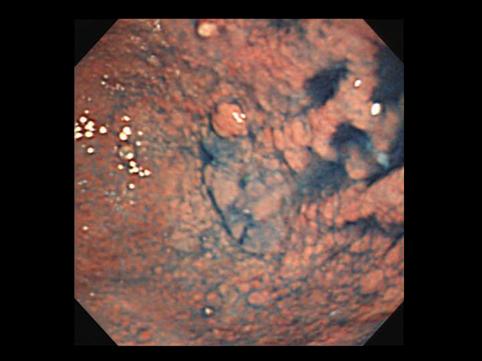

Criteria of Hist.ClassificationMalignant epithelial tumor/Adenocarcinoma

LocationStomach/More than one of above

Technique, MethodEndoscopy

Macroscopic TypesType 0/IIb (IIb+IIa) Superficial flat and elevated type

Size40 -

Depth of Tumor Invasionmucosa